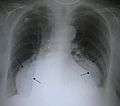

A large hiatus hernia on X-ray marked by open arrows in contrast to the heart borders marked by closed arrows